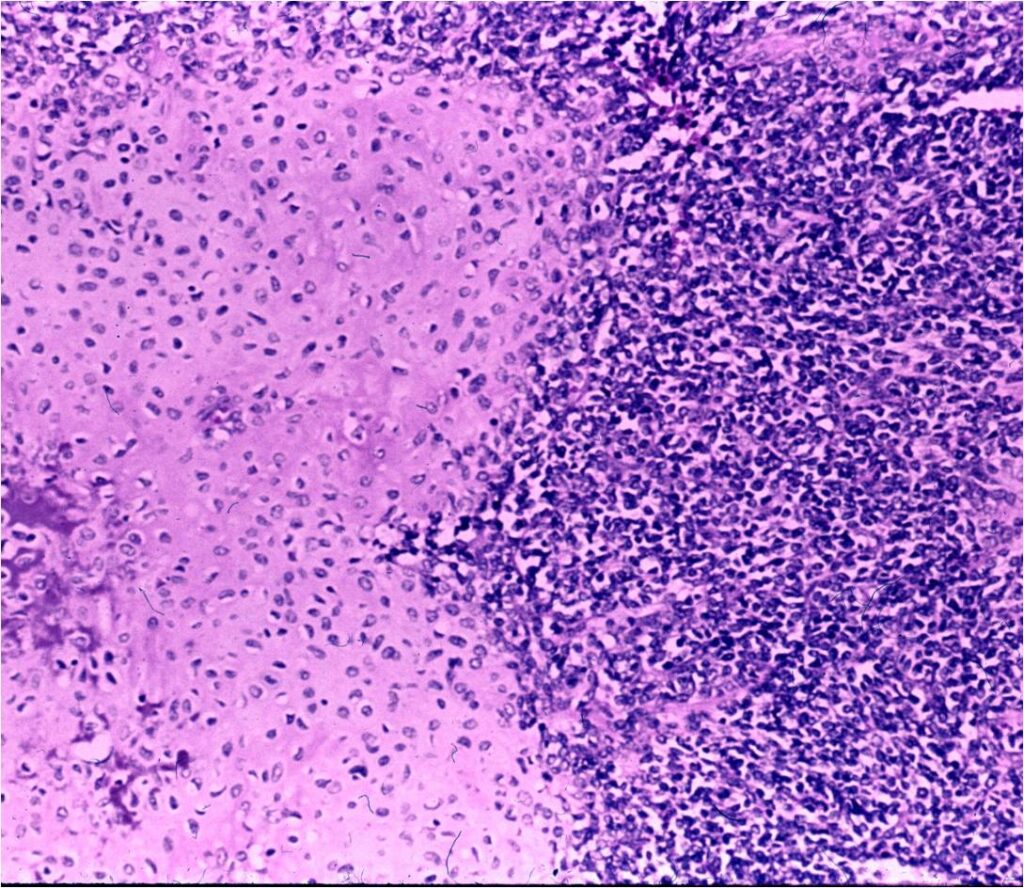

Microscopic Pathology

- Neoplastic cells may be small, round, oval, or spindle shaped

- Undifferentiated mesenchymal cells similar to Ewing sarcoma

- Low grade islands of cartilage scattered throughout the mesenchymal cells

- Usually only a small part of lesion

- Cytologically low grade

- Usually sharply demarcated from surrounding stroma

- Stain S-100 positive

- Cells within cartilage

- Tend to have round or ovoid nuclei

- Lacunae are poorly formed

- May contain islands of collagen resembling osteoid

- Lesions are vascular and often have large, anastomosing vessels that impart hemangiopericytoma-like pattern

(Right Arrow) Cartilaginous Component